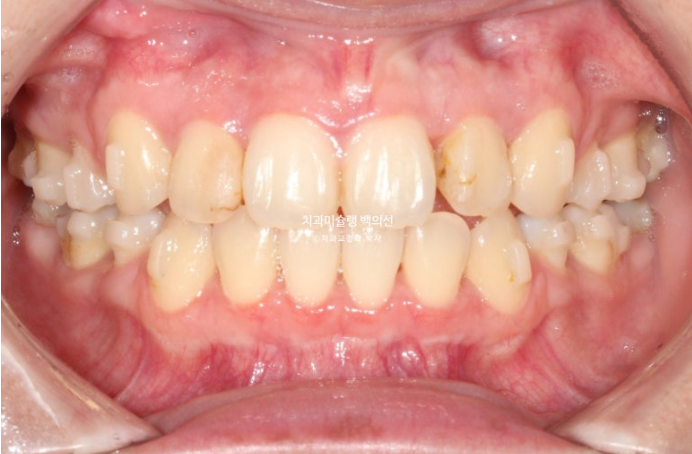

23년 7월 교정치료를 위해 내원한 20대 환자분입니다.

오래 전 비발치교정을 했던 이력이 있습니다.

앞니는 가지런한 편이며 중심선도 거의 맞습니다.

교합은 좋은 상태이고

치열도 꽤 가지러한 편입니다.

입안 사진만 보면 재교정을 왜하나 싶겠지만 환자분이 재교정을 해서라도 고치고 싶은 것은

돌출입

거미스마일 입니다.

돌출입이 심한 경우 입술이 편하게 다물리지 않는 입술부전증을 동반하며, 사진과 같이 턱끝에 힘이 들어가 호두턱, 호두주름을 만듭니다.

결과적으로 턱끝이 무턱처럼 보이게 하죠.

거미스마일도 심한 편이었으며 돌출과 거미스마일 해소를 위해 작은어금니 4개를 발치하고 치료에 들어갔습니다.